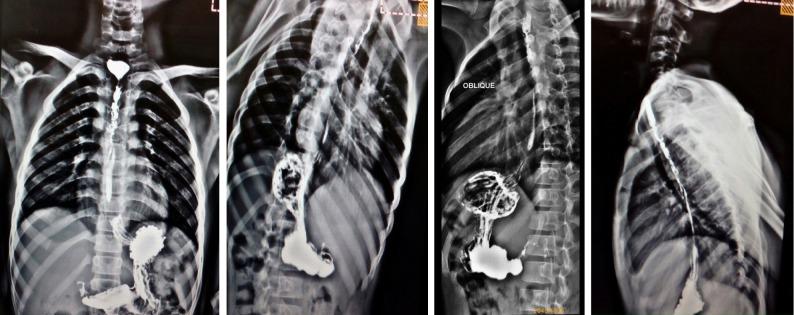

The mean age of the enrolled children was 5.9 ± 2.6 years; 90% of the patients had ingested an alkaline corrosive substance (potash). The total number of endoscopic dilatation sessions were ranging from 16 to 100 with mean number of sessions was 37.2 ± 14.9. Histopathological examination of the specimens showed that 85% of patients had evidence of chronic oesophagitis (group A) in the form of basal cell hyperplasia, hyperkeratosis and subepithelial fibrosis. Thirteen percent of the patients had evidence of reactive atypia (group B) in the form of severe neutrophilic intraepithelial inflammatory cellular infiltration, and 2 patients (2%) had mild squamous dysplasia (group C); we rebiopsied these two patients 6 mo after the initial pathological assessment, guided by chromoendoscopy by Lugol's iodine.

纳入儿童的平均年龄为 5.9 ± 2.6 岁;90%的患者摄入了碱性腐蚀性物质(钾)。内镜扩张次数从 16 次到 100 次不等,平均次数为 37.2 ± 14.9 次。标本的组织病理学检查显示,85%的患者有慢性食管炎的证据(A 组),表现为基底细胞增生、角化过度和上皮下纤维化。13%的患者有反应性异型增生的证据(B 组),表现为严重的中性粒细胞上皮内炎症细胞浸润,2 名患者(2%)有轻度鳞状异型增生(C 组);我们在最初的病理评估后 6 个月,根据卢戈氏碘染色的 chromoendoscopy 对这两名患者进行了再次活检。